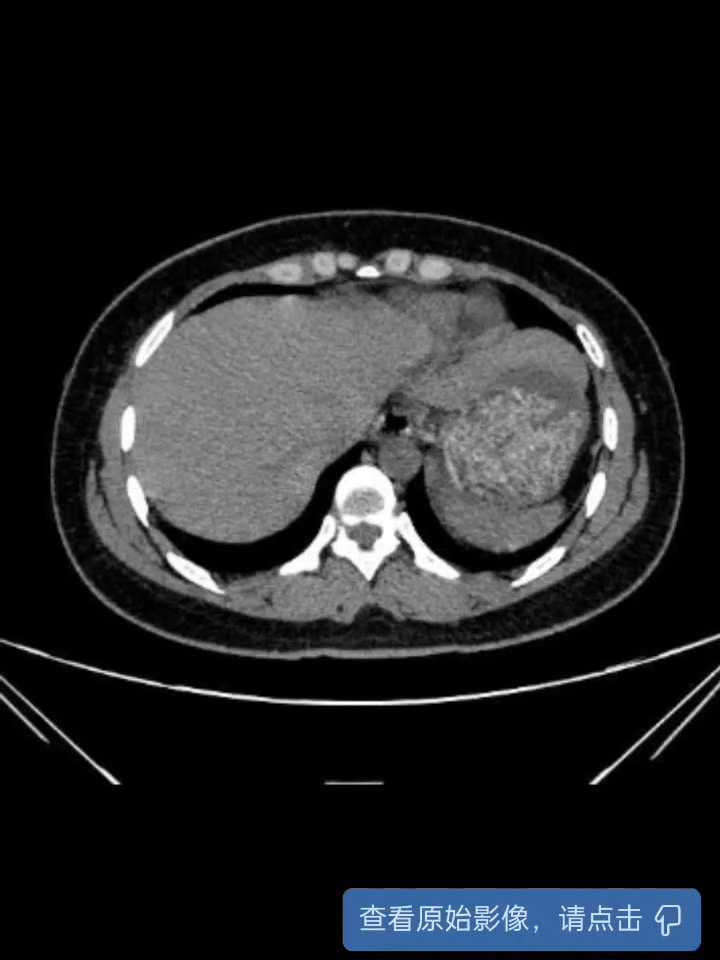

术后复查CT:

【治疗经过及结果】:入院后完善术前检查无明显手术禁忌症,次日行经尿道输尿管镜碎石术,术中证实左侧重复肾盂输尿管畸形,镜检两条输尿管均通常,分别两条通道置管。

术前比较担心其中有一条输尿管开口汇合处有狭窄,结石上移后可能无法进一步处理结石,所幸两处开口通过性尚可,但有一条类似于侧端汇入。